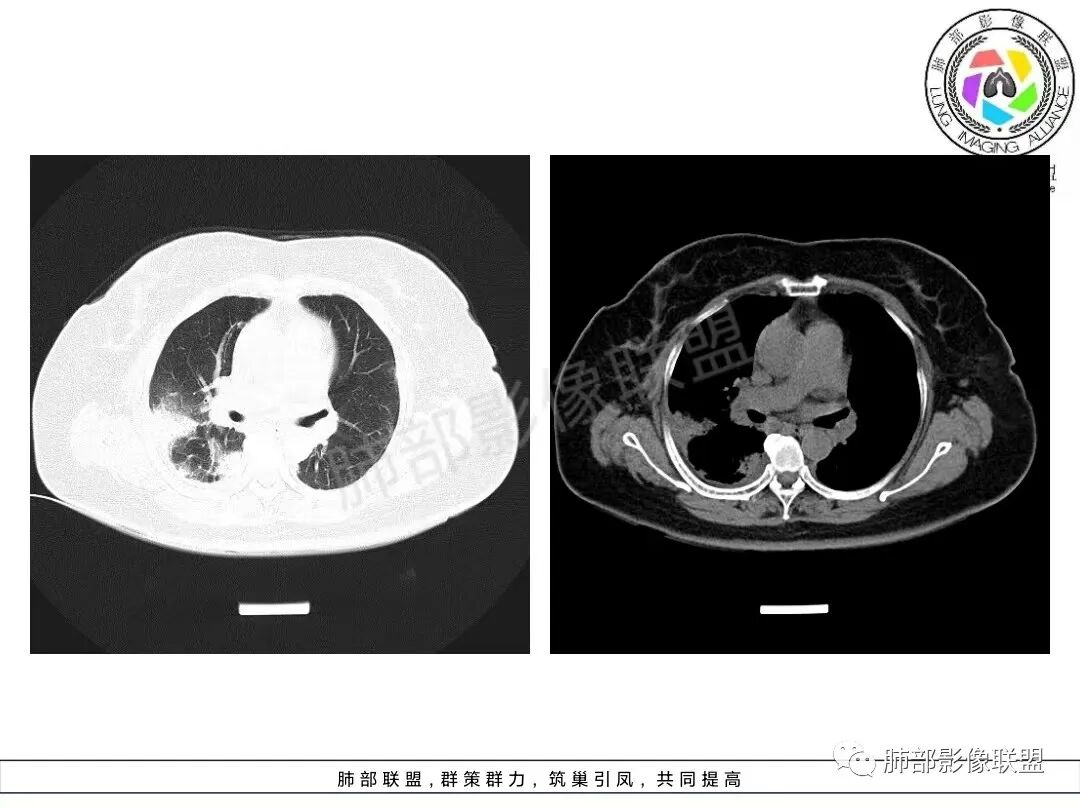

1、临床特点:70岁女性,务农。咳嗽咳痰伴气急20天。症状逐渐加重。有高血压病史。入院查体:体温37.5℃,急性面容。白细胞、CRP、红细胞沉降率升高。血糖高,CEA升高、余肿瘤标志物正常。ANCA检查阴性。血培养阴性,支气管灌洗液培养、真菌检测、抗酸杆菌均阴性。

2、影像特点:双肺胸膜下为主、多发斑片影、结节样实变影及磨玻璃样密度影,大部分病灶边缘平直、边界清,磨玻璃密度病灶内可见细网格影,部分病灶内可见支气管扩张表现,部分支气管直达远端,部分中断于病灶中部。部分病灶有侧向融合趋势。

3、病例小结:老年女性,咳嗽咳痰伴气急逐渐加重,入院后有低热。部分炎性指标升高,肺部片影,可以符合感染性病变,但是血培养、支气管灌洗液培养等检查无阳性表现。但仍影警惕隐球菌感染,患者临床表现相对轻微,胸膜下病灶,磨玻璃影等。

影像上双肺多发磨玻璃影及实行密度影,对称分布趋势,op样改变,结缔组织相关性疾病需要排除。临床上可进一步查皮肌炎相关指标、仔细进行体格检查看看患者皮肤等情况。